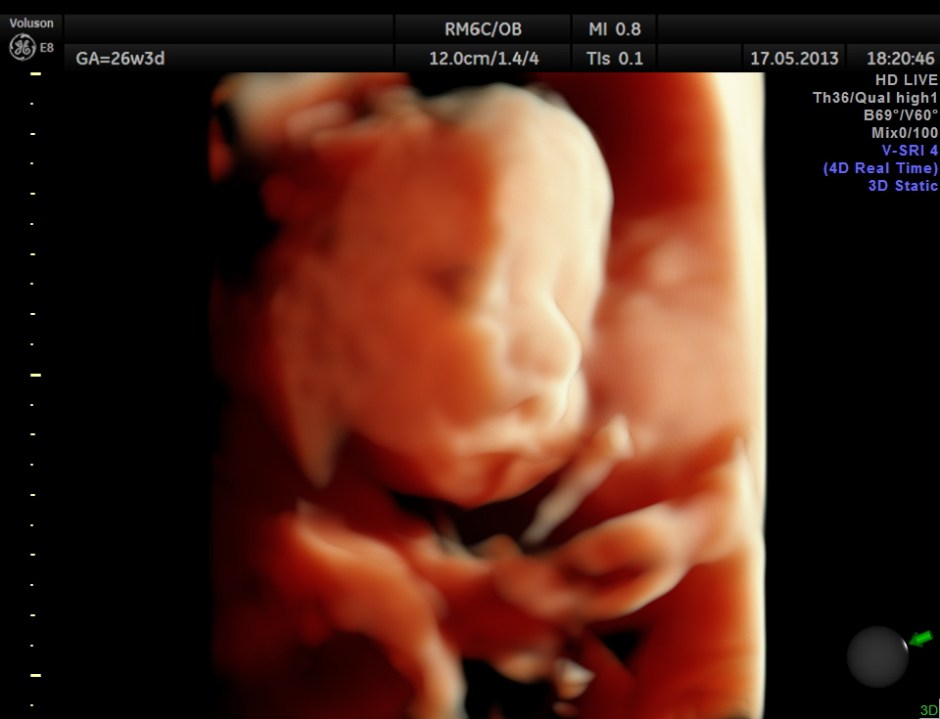

The following images show the face and the palate.

This fetus did not show any oro-facial clefts ; heart and spine appeared normal.